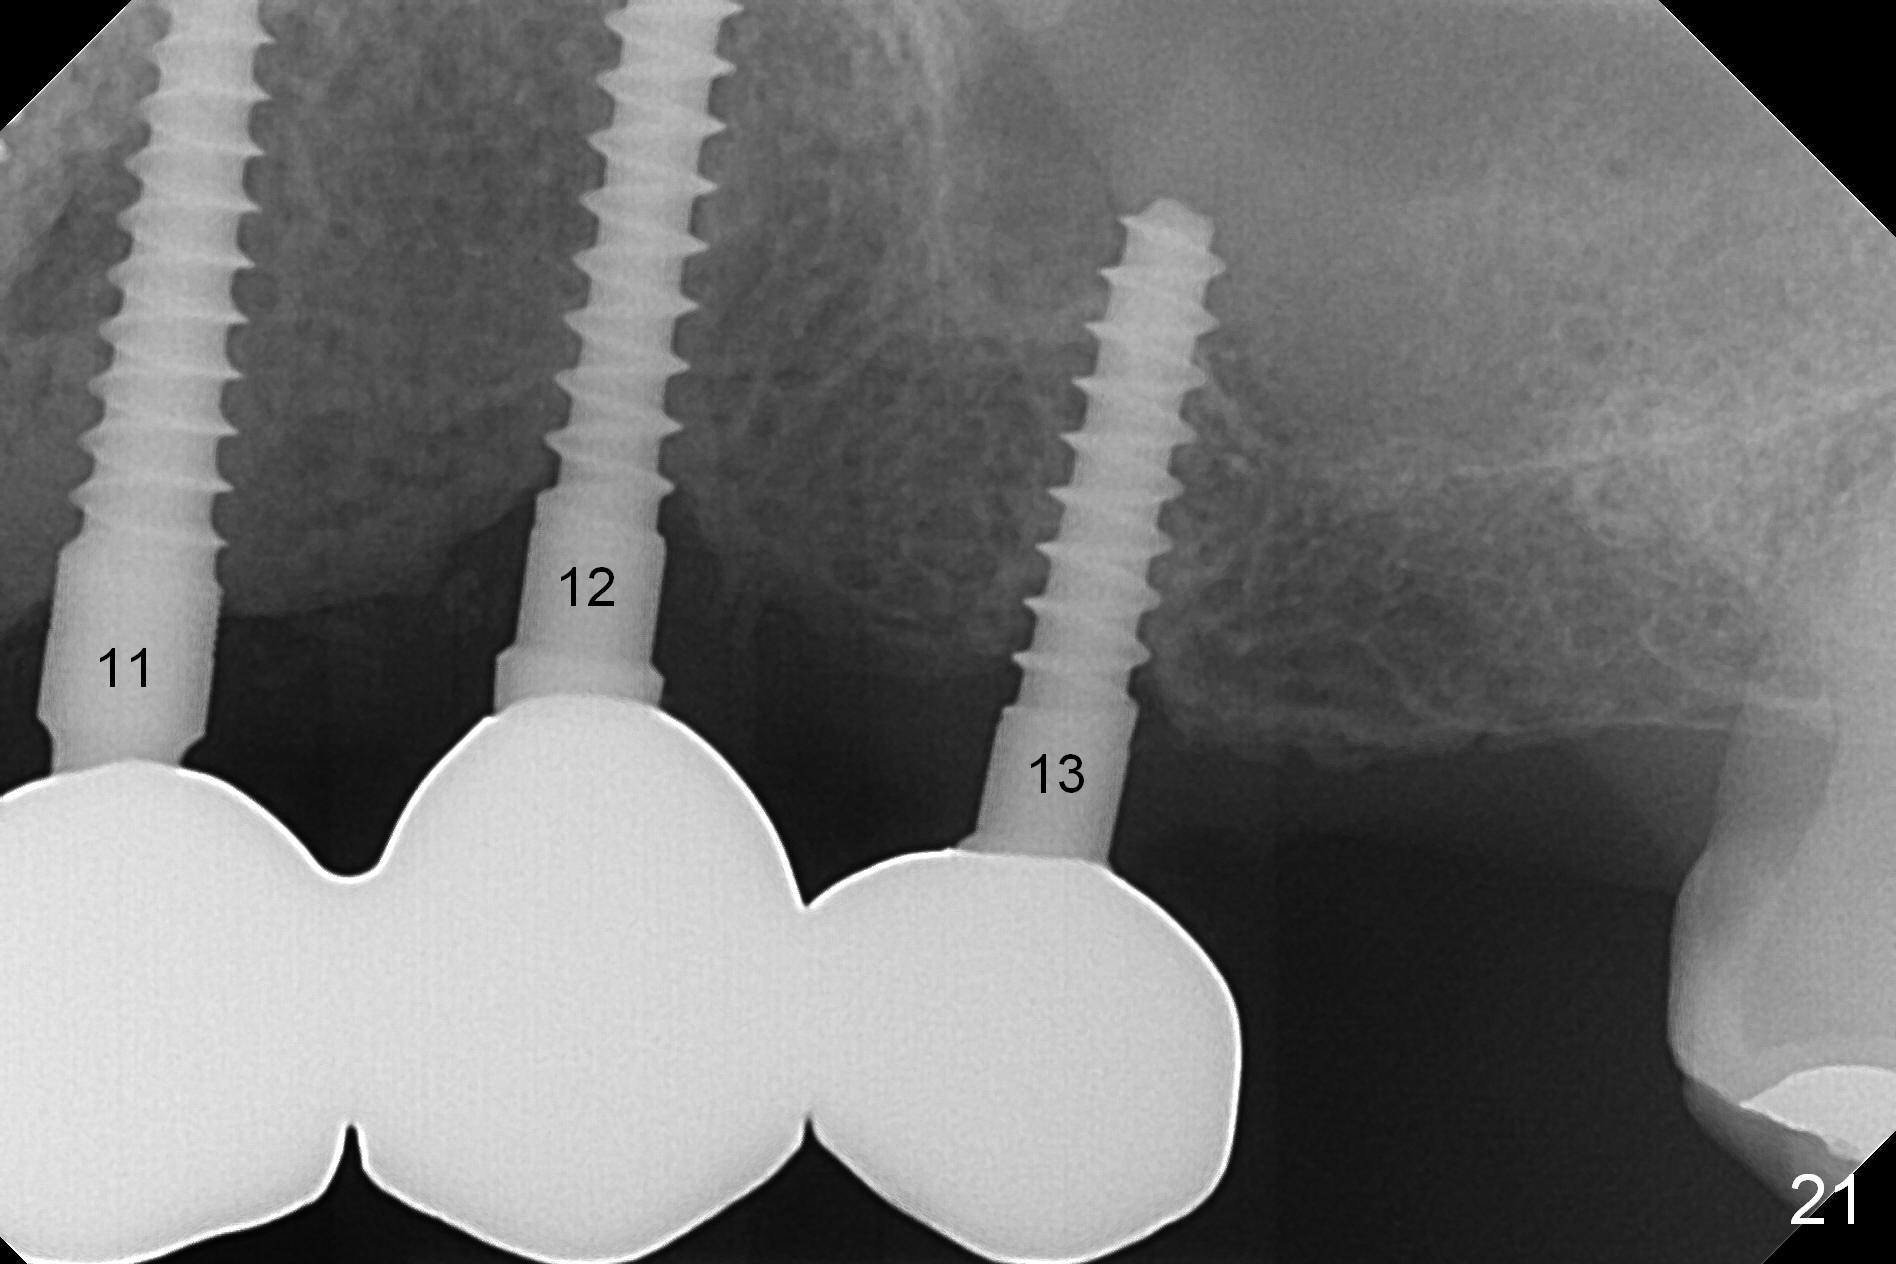

Six months post cementation, the tooth #9 becomes symptomatic.  Is it possible that the implant at #10 is too close to the root of #9?  It is asymptomatic after pulpotomy, but the tooth fractures equi/supragingivally.  Two PAs taken while RCT show osteointegration at #10-12 (Fig.18,19).  While the bone density increases at #10 regular implant, there is minimal bone loss around the 1-piece implants 13 months post cementation (18 months postop, Fig.20,21).  The gingiva remains healthy 19 months post cementation (Fig.22).  76岁病人突然打电话说一个植牙牙冠松动,其实9号牙(自然牙)折裂,6,10-13号牙植牙好像没有骨质吸收(图二十三至二十五),10-13牙位牙龈健康(图二十六,行使功能五年)。9号牙牙冠重新粘固后,显示前牙深覆合,深覆盖(图二十七,二十八)。如果再次脱落需要植牙,选择一段式有助于植入和修复,因为植体和基台直径小。两段式植牙相对基台直径至少4,或者4.5毫米,前牙修复显得笨重。由于9,10牙根和植体接近,9号牙植体需要偏小而长,3x14或者15毫米(图二十九)。